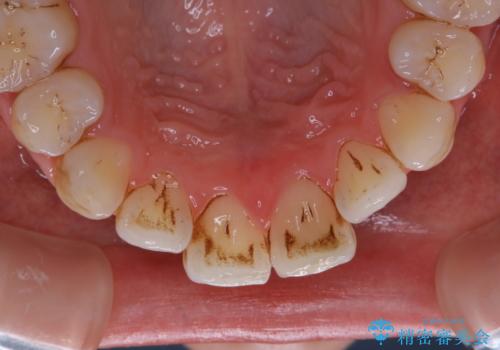

1年ぶりにPMTCで歯の着色落とし

- しばらく歯科医院へ行けなかったため、しっかり着色や汚れを落として欲しいとのことで来院されました。全体的に着色や歯石が付着していたためPMTC60分コースを行いました。